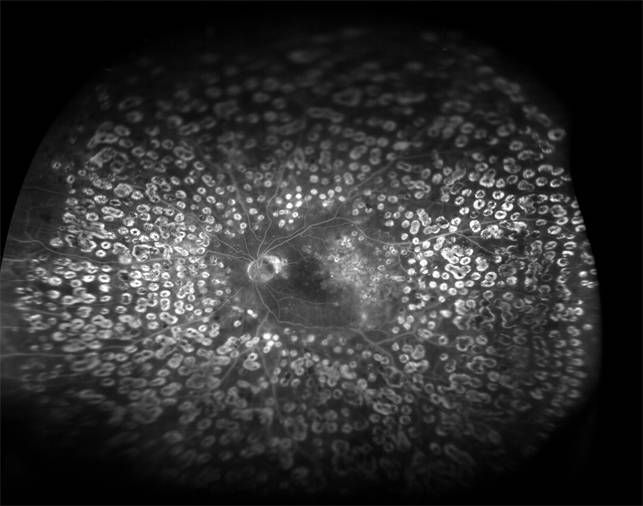

Важное значение для выявления не видимых при офтальмоскопии изменений сетчатки, определения показаний к лазеркоагуляции сетчатки и возможных зон её проведения имеет флюоресцентная ангиография сетчатки.

Флюоресцентная ангиография является основным методом исследования, достоверно подтверждающим факт наличия и распространенность по площади ишемических зон сетчатки. Необходимость съемки всей периферии глазного дна очевидна. Преретинальная и препапиллярная неоваскуляризация легко обнаруживается на ангиограммах яркой гиперфлюоресценцией в результате экстравазального выхода красителя. Вследствие окклюзии перифовеолярных капилляров развивается ишемия макулы. Ишемическая макулопатия диагностируется при расширении центральной аваскулярной зоны в два раза по сравнению с нормальным ее диаметром (0,5 мм).